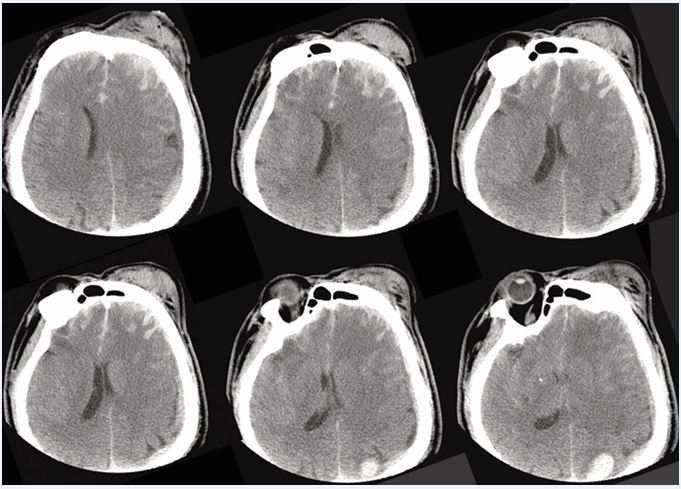

Timing practices vary internationally: the Western Trauma Association promotes early initiation when neuroimaging is stable, the Neurocritical Care Society supports chemoprophylaxis 24–48?h after a stable scan (and resumption ~24?h after neurosurgical procedures if stable), and ACS-TQIP 2024 emphasizes a 24–72?h window with repeated reassessment [11,14,15]. We adapt to age by accepting CPP toward 60–65?mmHg in frail or vasculopathic patients (escalating only if PbtO? or autoregulation data warrant) and to injury severity by starting LMWH as soon as the first stable repeat CT allows while using immediate mechanical prophylaxis during any mandated delay. In the present case, intracranial hypertension was controlled medically without craniotomy; because the vesicle/ inflammatory responses arise from parenchymal injury per se, the mechanistic rationale for timely fixation and early HO vigilance applies directly (Figure 4).

https://www.jscimedcentral.com/public/assets/images/uploads/image-1766058751-1.JPG

Figure 4 Admission head CT (axial slices) Representative axial images demonstrating parenchymal injury and edema in the acute phase of TBI.